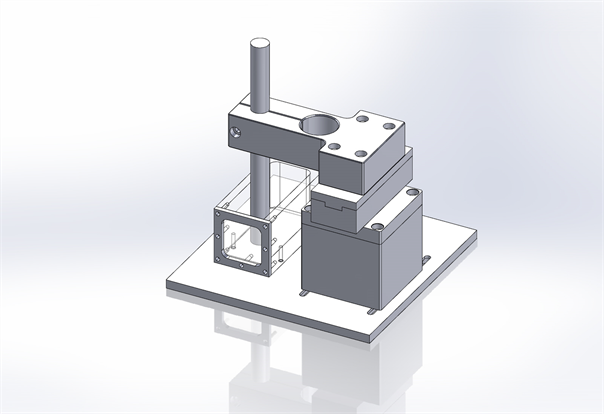

A schematic view of the complete setup is shown in Figure 2. The central axis depth ionization measurements were performed in a water tank with dimensions 92 × 40 × 40 mm3.

Central-axis depth-ionization measurements were performed in a water tank with 0.1cc ionization chamber (Model IC-18, Far west) having walls made of Shonka A150 plastic. The water tank has a 0.13 mm thick kapton entrance window through which the proton beam was incident. In order to keep ionization chamber at one place in a vertical position and make it water proof, a thin plastic tube with tissue equivalent material was positioned in the center of the field as seen in Figure 1. The ionization chamber was always positioned in the center of the circular field of diameter 30 mm with the phantom surface at iso-center. To understand the effect of silicone oil on the physical characteristics of proton beam, three sets of measurements were made. In the first run, the Bragg-peak measurements were made in a water tank (simulating the tissue-equivalent of a normal eye). In the second run a small tank filled with silicone oil was placed

Figure 2. A schematic view of the experimental setup. The ionization chamber is placed in a thin tissue equivalent tube attached to the tank.